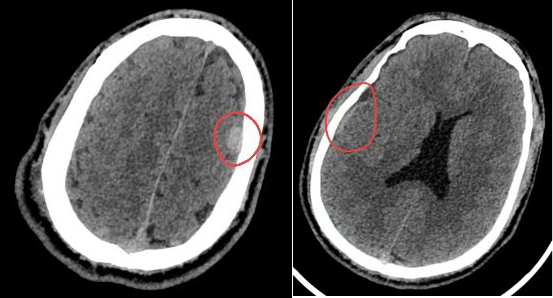

检查结果让所有人都捏了把汗:CT 显示董某右外侧裂池、右颞顶叶部分脑沟,以及大脑镰、小脑幕密度增高,提示为 蛛网膜下腔出血;更危险的是,他还伴有左额部硬膜外小血肿,且血肿仍在持续增大,随时可能引发颅内压升高、脑疝等致命风险。